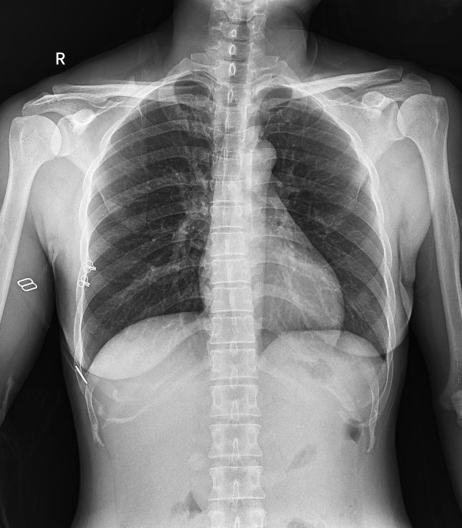

普利德醫(yī)療自主研發(fā)的新一代數(shù)字化X線透視攝影系統(tǒng),可應(yīng)用于DR攝影、數(shù)字透視、數(shù)字造影以及可視化精準(zhǔn)DR拍片等多種臨床X線檢查領(lǐng)域。

● 高效動(dòng)態(tài)平板技術(shù),圖像不會(huì)有幾何畸變,提供高分辨率和精確的圖像,為醫(yī)生臨床診斷提供精準(zhǔn)依據(jù);

球管傾斜攝影角度-45°~45°,滿足臨床各部位各角度的攝影需求。如:髕骨軸位、頸椎正位、骶尾椎、鼻竇瓦氏位、梅氏位等部位檢查。

拉伸自如:SID電動(dòng)拉伸,最長(zhǎng)可延伸至1.8米,滿足放射科室各種拍片距離的需求。如:GBZ 70-2015職業(yè)性塵肺病的診斷標(biāo)準(zhǔn)中對(duì)胸片拍片距離1.8米的要求。